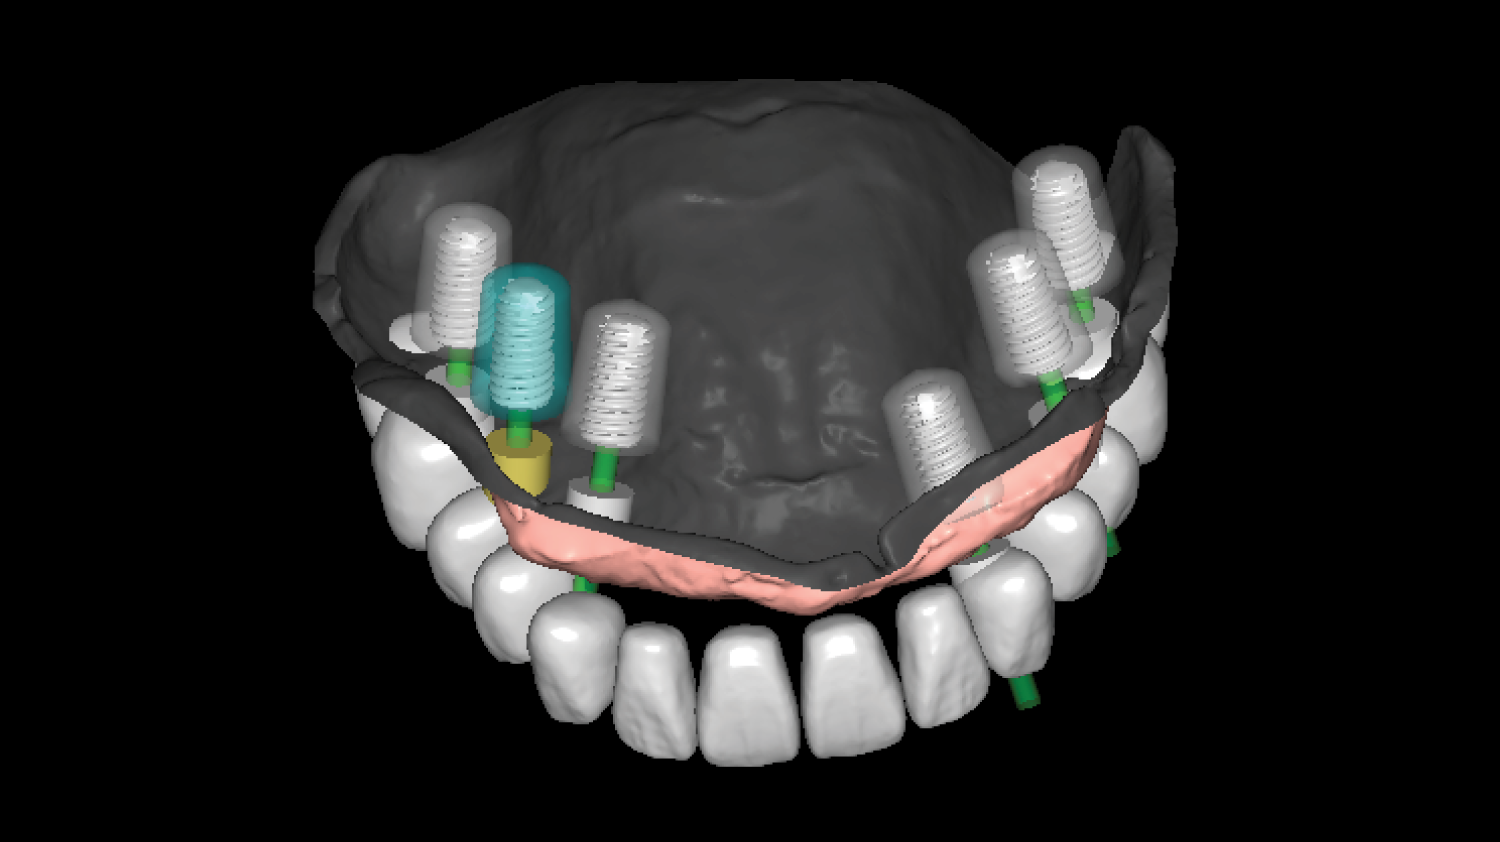

Course Overview

This course presents simplified yet clinically precise workflows for edentulous patients, enhancing both efficiency and patient comfort. Using the JB Tray, participants will learn how to combine custom tray fabrication, final impression, and jaw relation records in a single appointment, supported by digital processing and a live demonstration.

The program also introduces the JB Fork system, which integrates CBCT imaging and anterior reference points to enable one-step surgical stent fabrication without repeated impressions. Through practical demonstrations, attendees will see how this approach streamlines implant surgery while maintaining accuracy. The course concludes with insights into plasma surface treatment in implantology, highlighting its role in advancing clinical outcomes.

• One-Step Surgical Stent Fabrication Using JB Fork and CBCT.

Director’s Clinical Cases

Director’s Clinical Cases

One-Step Surgical Stent Fabrication with JB Fork

• Radiopaque JB Fork and the role of six anterior reference points: Registration with CBCT and integration with facial scanners

• One-step avatar creation without additional clinical procedures

• Surgical stent design and its application in implant surgery

• Live demonstration of JB Fork application in a patient case

Surgical stent design with all guides and implant studio software. (Prof Huh) |

One-Step Surgical Stent Fabrication with JB Fork

• Radiopaque JB Fork and the role of six anterior reference points: Registration with CBCT and integration with facial scanners

• One-step avatar creation without additional clinical procedures

• Surgical stent design and its application in implant surgery

• Live demonstration of JB Fork application in a patient case

Surgical stent design with all guides and implant studio software. (Prof Huh)